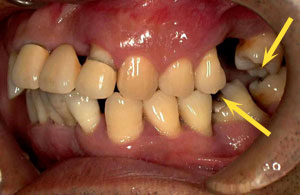

計測データがあれば効果的な咬合圧の負担軽減法を客観的に選択することが可能になります。さらに、選択された治療法の術前、術後の負担軽減効果を評価することもできます。負担軽減法は咬合調整からスプリント(副木)を装着する方法まで色々あります。動揺歯の周囲の歯を含めてスプリント(副木)を装着する方法は最も効果的な負担軽減法です。この治療法は歯の動揺が停止するだけでなく歯周組織の破壊も改善します。7-6(Photo-1~Photo-3)

With measurement data, it becomes possible to objectively select effective occlusion pressure burden reduction method.In addition, it is possible to evaluate the effect of reducing the burden of preoperative and postoperative burden of the selected therapy. There are various ways to reduce burden from occlusal adjustment to a method of installing a splint. The method of attaching the splint including the teeth around the loose tooth is the most effective way of reducing the burden. This treatment not only stops tooth oscillation but also improves periodontal tissue destruction. 7-6(Photo-1~Photo-3)

その結果、1本の歯が傾きますと両隣の歯だけでなく対合歯にも影響が波及し歯並びの乱れが目立つようになります(Photo-1)また前歯では反っ歯になり口を閉じて歯が見えるようになります(Photo-2)